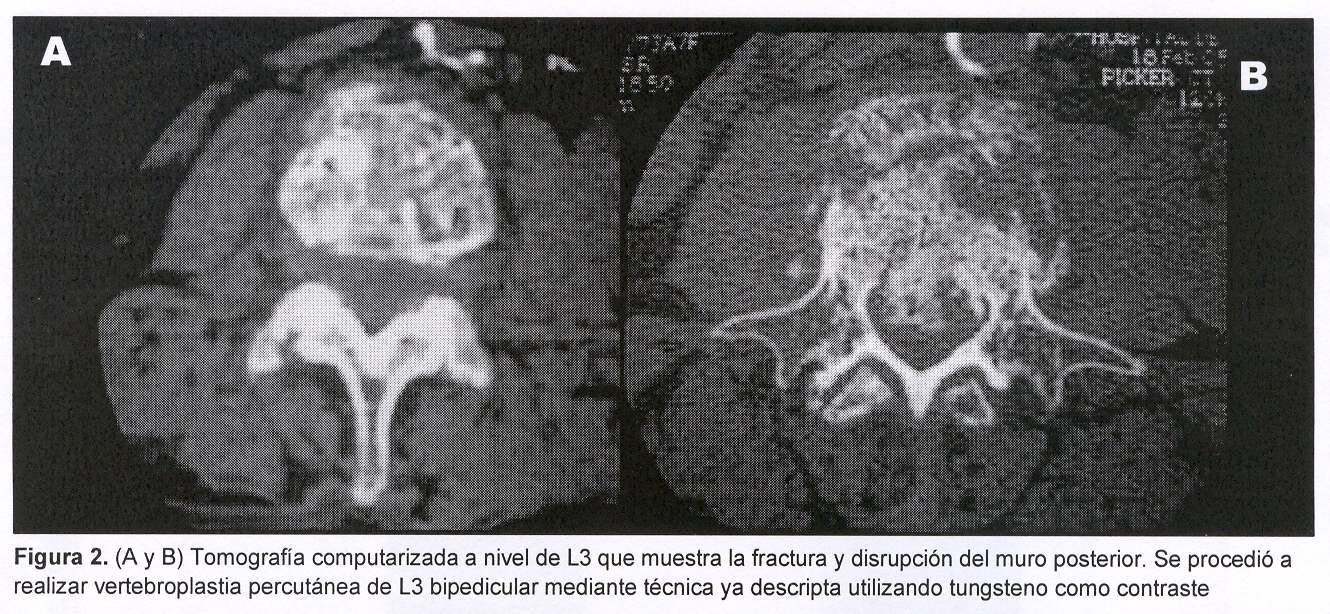

Es estudiada mediante radiografía y TC de columna vertebral lumbosacra que muestran: desmineralización difusa y disminución de la altura del cuerpo vertebral de L3, con colapso del platillo superior y pérdida de continuidad de la cortical ósea del muro posterior (figuras 1, 2 y 3).

Se procedió a realizar vertebroplastia percutánea de L3 bipedicular mediante técnica ya descripta utilizando tungsteno como contraste (figura 4).